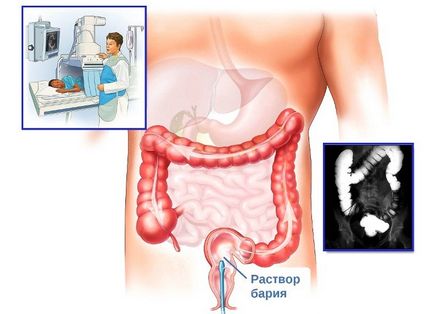

Рентген повинен проводитися після того, як пацієнт підготується до процедури. Перед діагностикою хворий не повинен їсти мінімум за 8 годин.

В організм вводиться спеціальна барій завись. Завдяки такій рідини під час обстеження можна чітко побачити стінки стравоходу. Барій завись створює контраст, що дуже важливо для рентгеноскопії. Це дозволяє точніше поставити діагноз, а також отримати більш точну картину при новоутворенні.

Рентген допоможе диференціювати кільця Шацького від можливого випинання стінок верхнього відділу травної системи або попадання сторонніх предметів. Зазвичай процедура триває близько 45 хвилин. Після цього пацієнтові дають випити велику кількість води, щоб сульфат барію міг швидше вийти з організму.